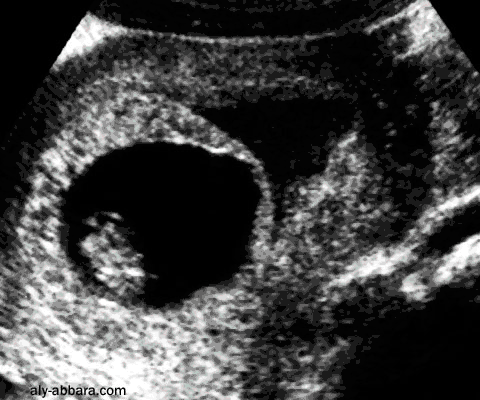

Grossesse et menace d'avortement

Grossesse de 9,5 semaines d'aménorrhée évolutive avec une menace d'avortement se manifestant par

un décollement du tissu trophoblastique et de métrorragie